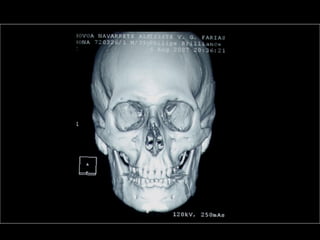

AmeloblastomaAmeloblastoma

Ameloblastoma

Neumólogo: Dr. Crescenciano González OlivaresNeumólogo: Dr. Crescenciano González Olivares

Trismus importante debido a queTrismus importante debido a que

El tumor ya rompió el hueso com-El tumor ya rompió el hueso com-

Pacto de la cara interna de laPacto de la cara interna de la

Mandíbula y empezó a tomar elMandíbula y empezó a tomar el

Músculo pterigoideo interno.Músculo pterigoideo interno.

Sierra de GigliSierra de Gigli

Luxación de hemimandíbulaLuxación de hemimandíbula

Pieza quirúrgicaPieza quirúrgica

Plantilla flexible para dar forma previa al implante

Se respetó el cóndilo para anclar la prótesisSe respetó el cóndilo para anclar la prótesis

Límite tumoralLímite tumoral

Area de lisis ósea a nivel de la líneaArea de lisis ósea a nivel de la línea

Miliodes que contracturó los músculosMiliodes que contracturó los músculos

Milohioideo y pterigoideo internoMilohioideo y pterigoideo interno

Dificultando la deglución y determinandoDificultando la deglución y determinando

Trismus importante.Trismus importante.

Pieza en proceso de examen por histopatologíaPieza en proceso de examen por histopatología

Dr. Ismael Espejo Plascencia PatólogoDr. Ismael Espejo Plascencia Patólogo

48 horas de post-operatorio48 horas de post-operatorio